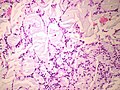

Myxoid chondrosarcoma

Microscopic: Features:

DDx:

- Chondroid syringoma - These are dermal based, circumscribed and much smaller.

- Parachordoma.[10]

- Chordoma. (???)

- Myxoid liposarcoma.

- Metastatic myxoid carcinoma.